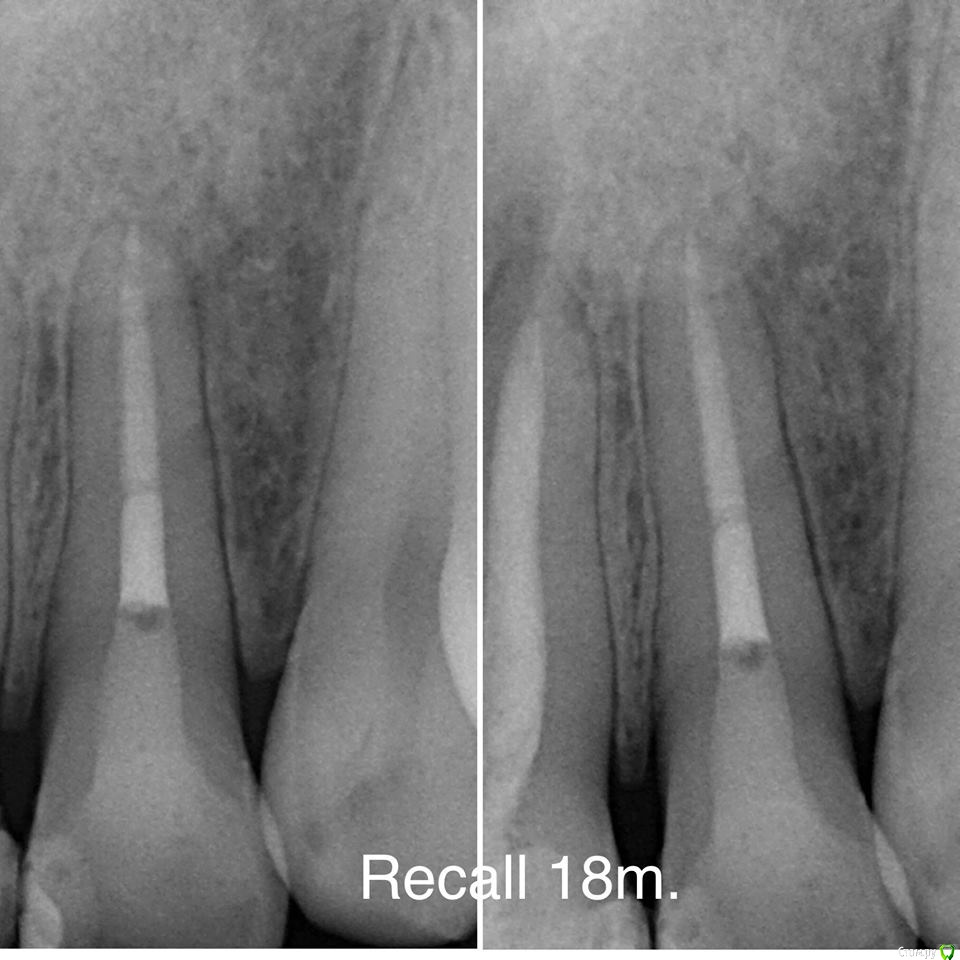

Гарриевич Опубликовано 2 октября, 2018 Автор Поделиться Опубликовано 2 октября, 2018 пришло время отчета 5 Ссылка на комментарий

DmitrySH Опубликовано 3 октября, 2018 Поделиться Опубликовано 3 октября, 2018 Закономерный результат достойной работы! 2 Ссылка на комментарий